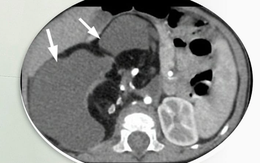

Phát hiện ung thư dạ dày sớm bằng cách nào?

Khi có triệu chứng lâm sàng nghĩa là ung thư đã ở giai đoạn tiến triển, không còn là giai đoạn sớm.